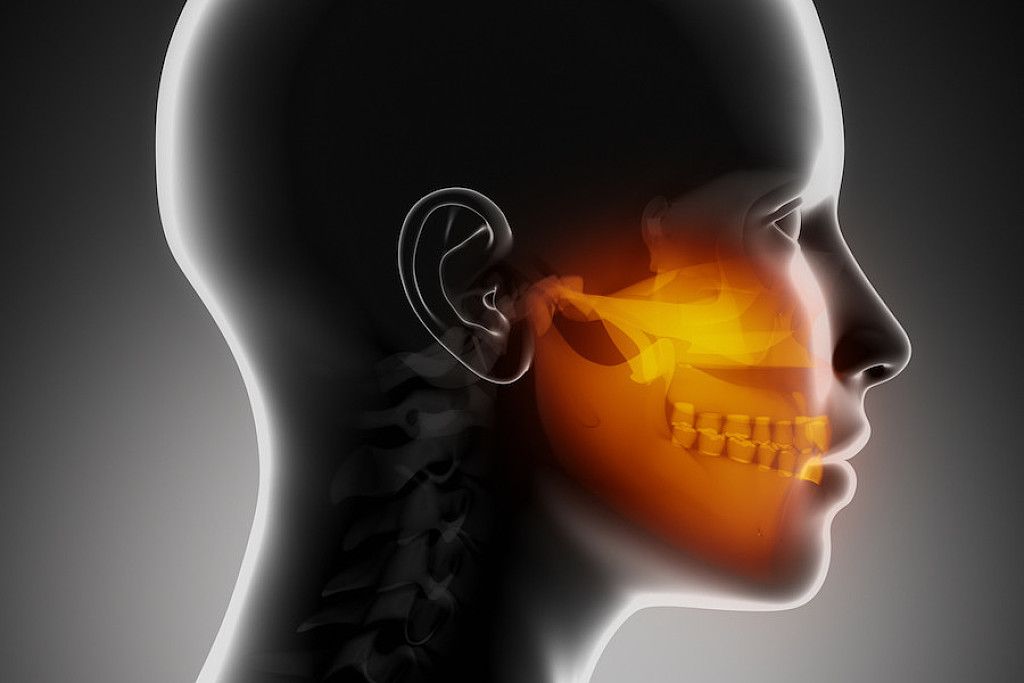

Swelling of the Jaw

A primary symptom of cancer in the jaw is swelling in the face, palate, or area of your jaw that supports your teeth. This swelling may be visible on the side of your face, but it can also occur inside your mouth. You may notice swelling in the roof of your mouth or beneath your teeth, depending on the location of the tumor. The growth of a tumor inside the bone may be the cause of this inflammation—and should be brought up with a dental professional as soon as possible.